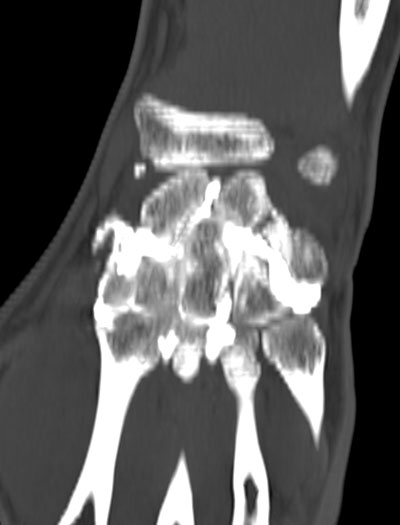

Poignet